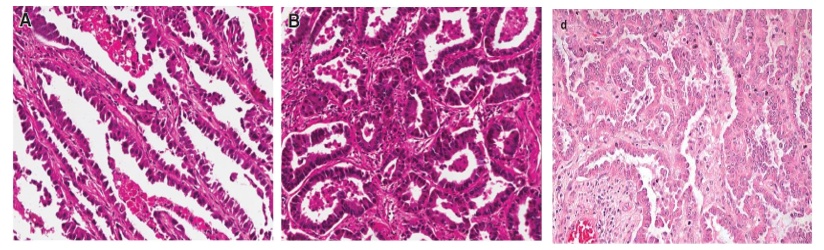

浸润性非粘液腺癌(INMA): 包括5种病理亚型,贴壁亚型最温和,预后非常好;微乳头亚型和实体亚型较凶狠,淋巴结转移可能大;腺泡亚型和乳头亚型居中。

从左至右:贴壁、腺泡、乳头

左:实体;右:微乳头